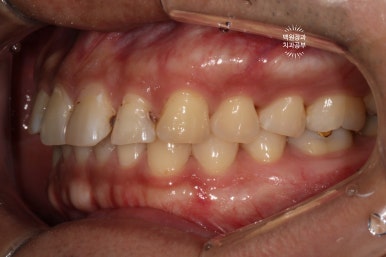

정면으로 보이는 곳은 기존 레진의 변색으로 인한 discoloration이 관찰되었고,

위턱 앞니 중 왼쪽 치아들은 옆면에 충치 (치아우식증)가 아주 선명히 보이고 있네요.

고개를 돌려서 우측을 보시면, 까맣 까맣하게 보이는 부위들이 있는데 대부분이 '레진 변색' 입니다.

고개를 돌려 좌측을 보시면, 우측에서 보이던 것과 달리 치아 표면이 깨져서 구멍이 나신 것을 보실 수 있죠?